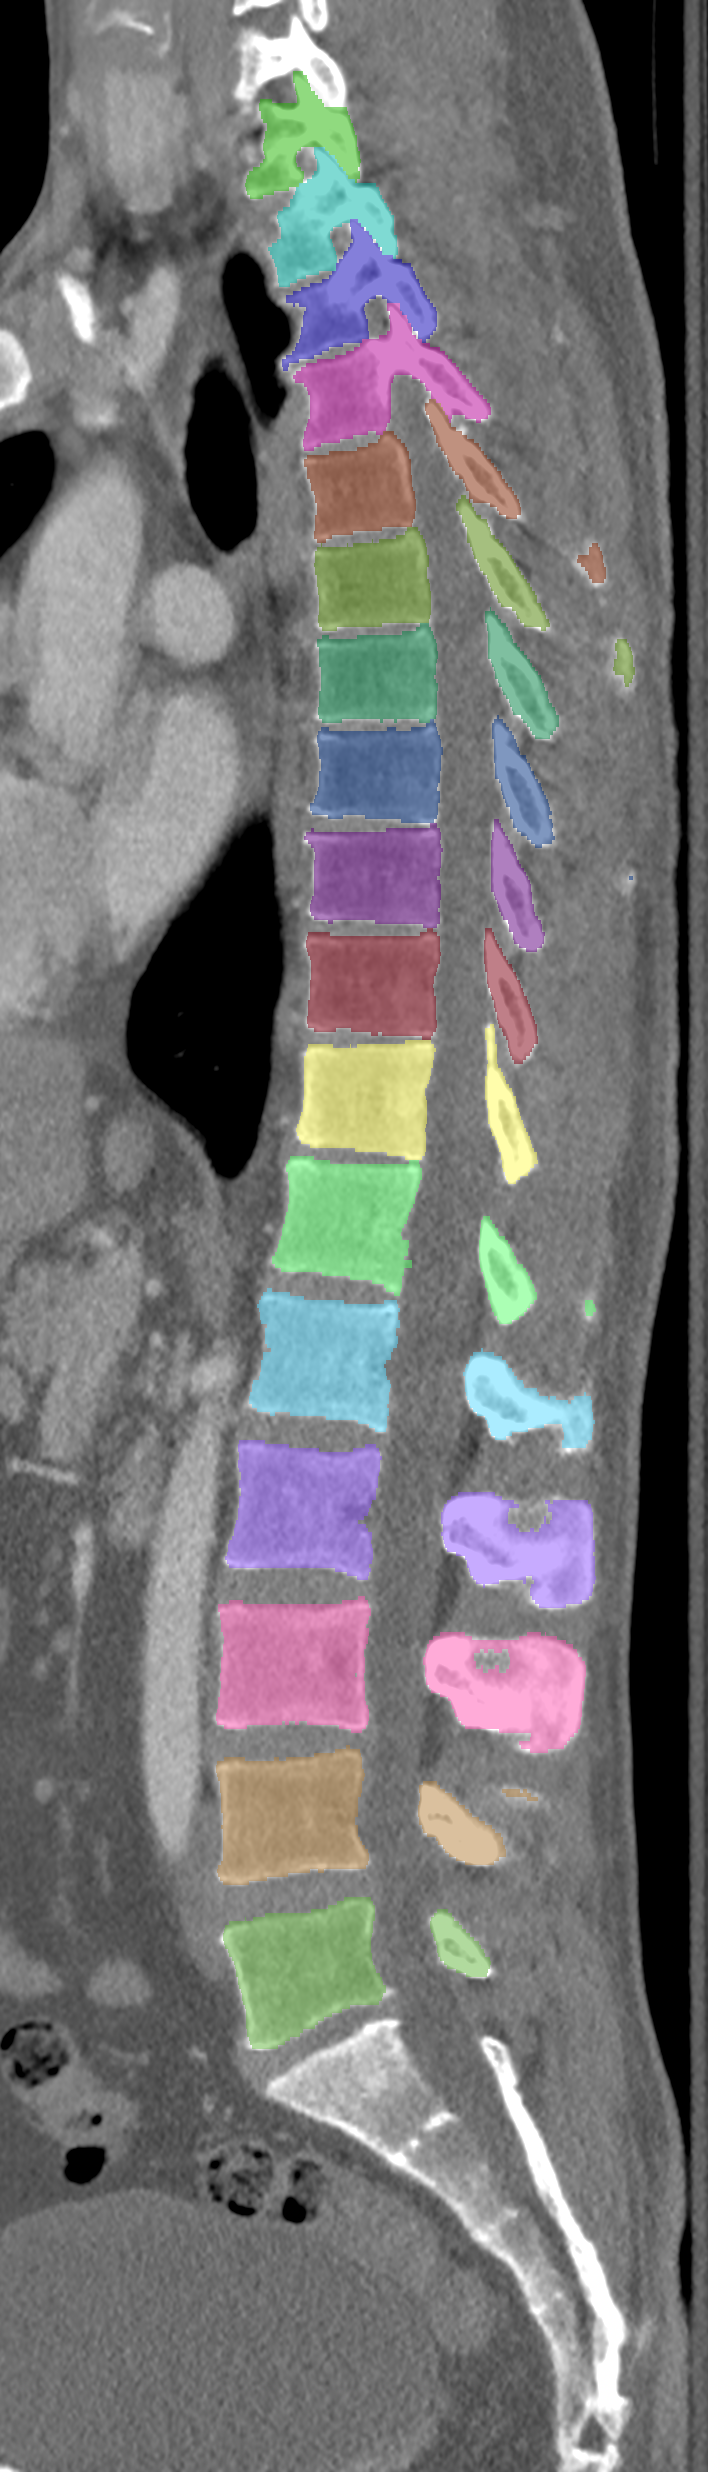

Normalized CT images and reference segmentations of thoracic and lumbar vertebrae from the CSI 2014 workshop

Description

This is the dataset of the vertebra segmentation challenge of the CSI 2014 workshop that was held in conjunction with MICCAI 2014.

- Vertebrae have been anatomically labeled (8 = T1, 9 = T2, ..., 24 = L5)